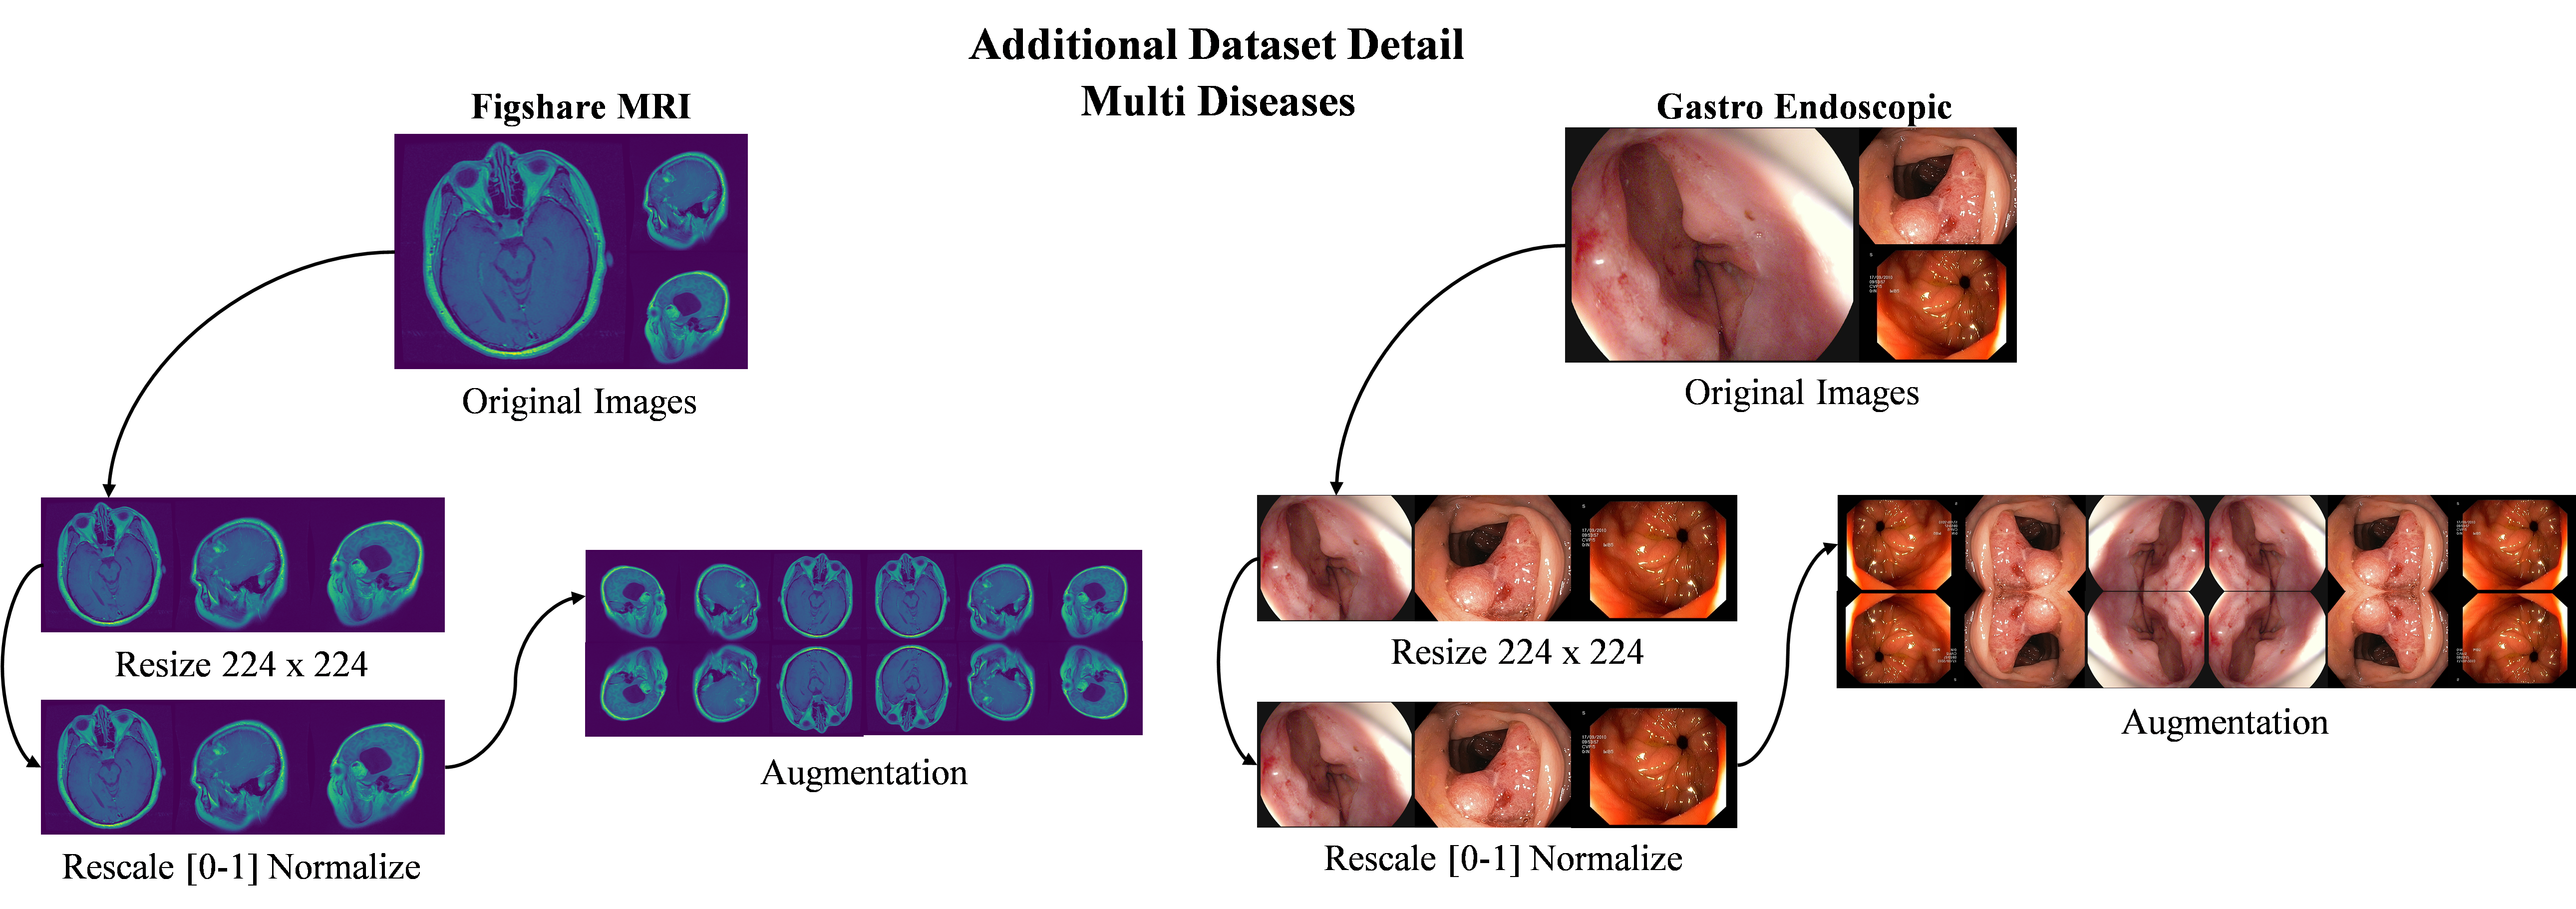

4.3 Dataset pre-processing

Dataset pre-processing is a crucial step in preparing data for effective model training, especially in the context of medical image analysis. This process involves several techniques [17], including resizing, rescaling, rotation, and flipping, which collectively enhance the robustness and diversity of the dataset. Resizing images ensures uniformity in dimensions by allowing models to process input efficiently without any distortion. Rescaling adjusts the pixel intensity values by normalizing them to a specific range [0-1], which can significantly improve the convergence of neural networks. Rotation introduces variations in the orientation of images by enabling models to become invariant to changes in perspective, while flipping both horizontally and vertically assists to simulate different viewpoints and minimize overfitting. By employing these pre-processing techniques, we not only enrich the dataset but also contribute to a more generalized model that performs better across a variety of real-world scenarios. This comprehensive approach efficiently prepares the data by establishing a strong basis for subsequent training and improving the overall model performance. Fig 8 displays the preprocess and augmented dataset samples of Kaggle multiclass dataset.

Refer to caption

Figure 8: Overview of preprocess and augmented dataset samples

4.8.1 Dataset Collection

Fig 13 displays sample images from Figshare brain tumor [45] dataset. In a standard brain MRI image, healthy brain structures appear normal. However, when dealing with brain tumors, we observe changes in tissue density, manifesting as varying signal intensities in the images. These changes often include tumor masses, areas of consolidation, and variations in texture. These anomalies tend to localize within specific brain regions, frequently affecting particular intellectual parts. To maintain the fair evaluation, we have utilized the same dataset distribution. Three primary categories of brain tumors include Figshare dataset. Among these, Glioma tumors account for a total of 1283 images, Meningioma tumors contribute to 566 cases, and Pituitary tumors make up 714 cases. A comprehensive GI endoscopic image dataset was created by combining curated gastrointestinal imaging datasets [45]. The proposed model for identifying GI ailments was trained and tested using this dataset. In order to depict various infection classifications, the dataset 396 images were divided into three groups of images such as Colorectal Cancer (139), Esophagitis (107), and Pylorus (150).

Figure 13: Additional multiclass dataset sample visualization